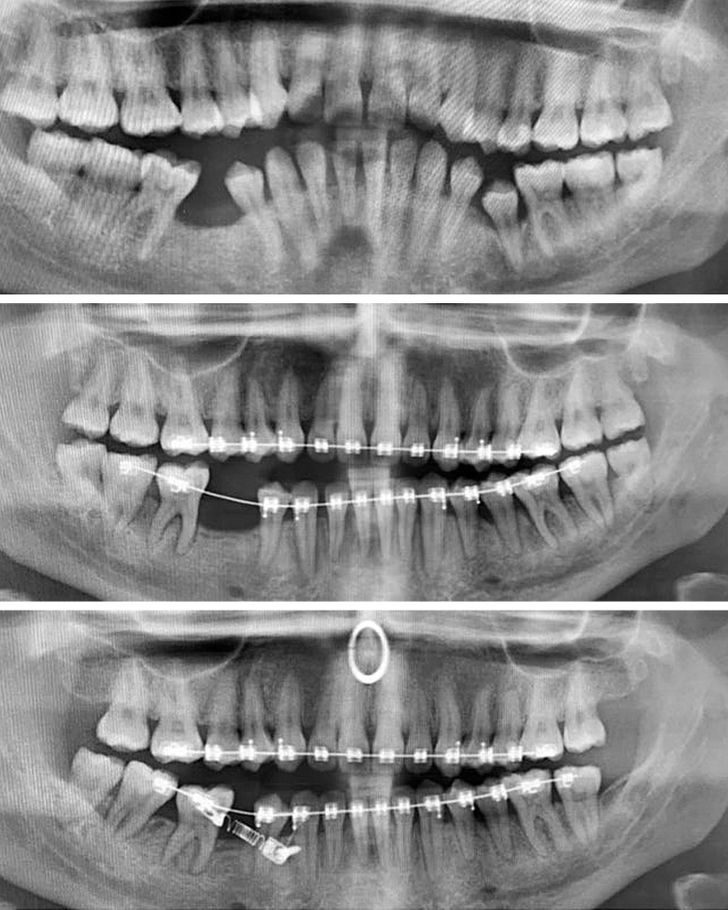

«Мои зубы до брекетов и спустя 2 года. Август 2018-го и август 2020-го»